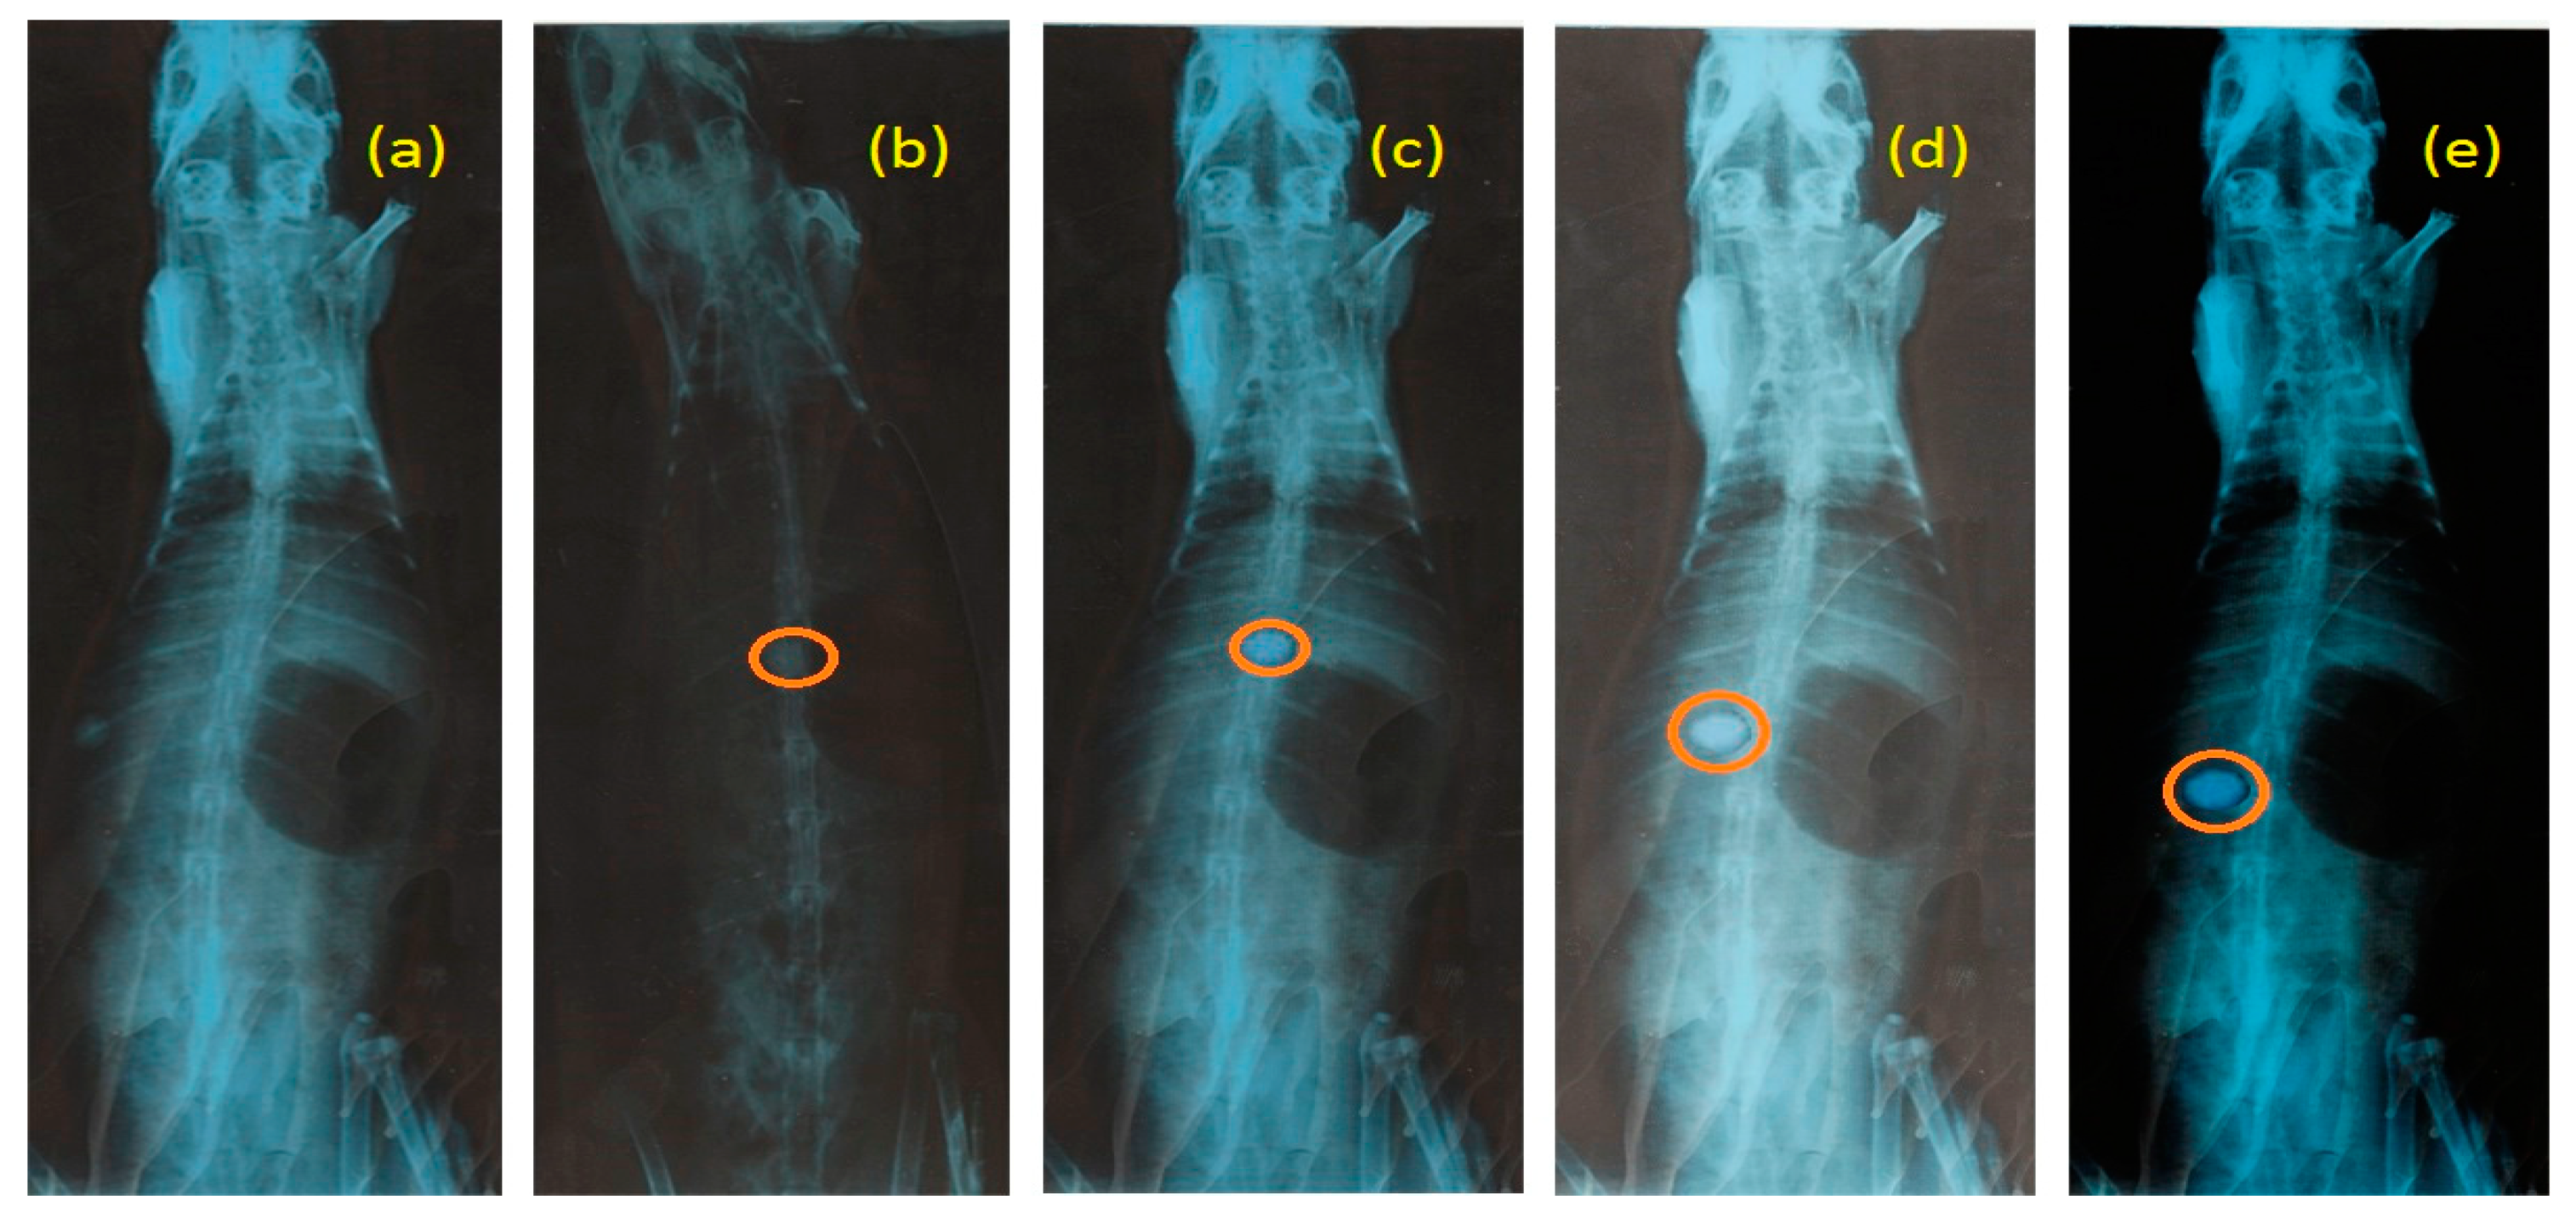

2.6.1. In Vivo Mucoadhesion Study

3.8. In Vivo Mucoadhesion Studies